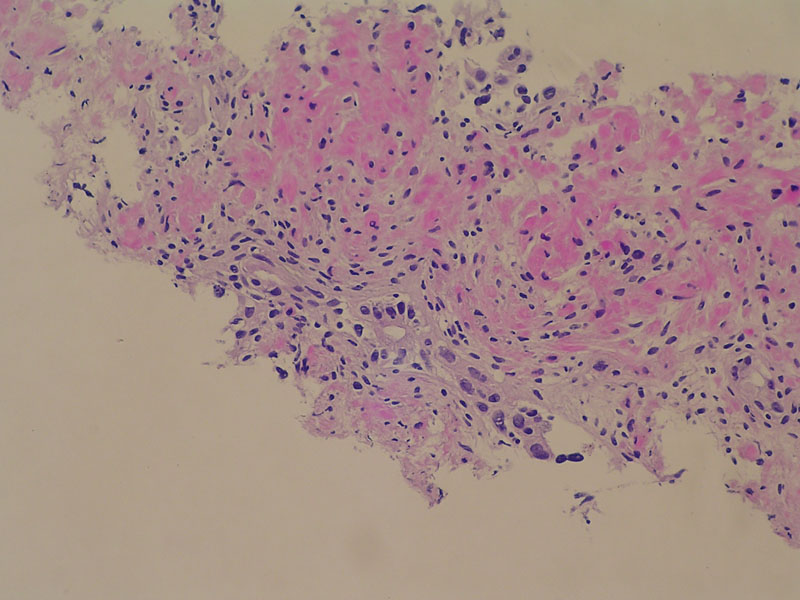

Caso Nº 2:

Varón de 26 años con lesión papilar única en vejiga. Sin recidiva por más de 2 años.

Diagnóstico:

Papiloma Vesical.